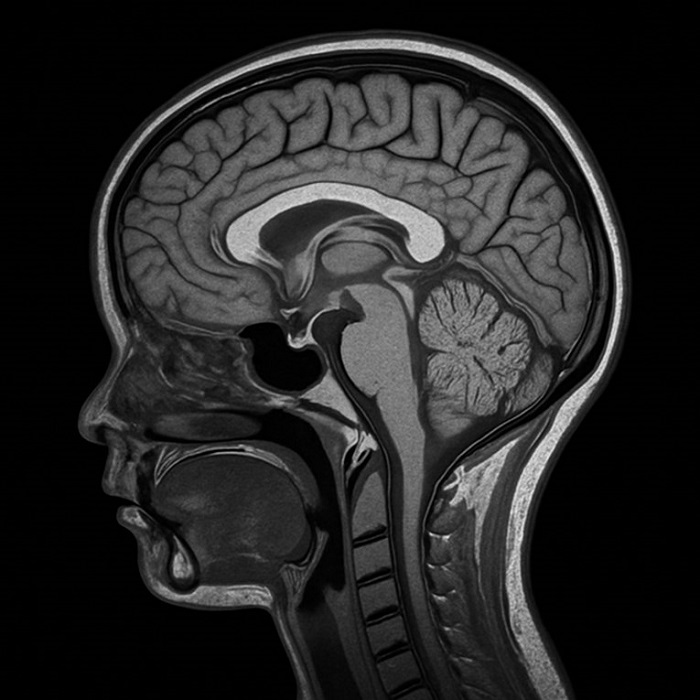

Во неа, научниците користеле, меѓу другото, податоци снимени со магнетна резонанца (МРИ) со цел да ја споредат дебелината на кортексот и другите анатомски карактеристики на мозокот кај деца од различни социоекономски услови.

Резултатите покажале дека децата од области со повисоко ниво на нееднаквост во приходите имаат помал вкупен кортикален волумен, помала просечна дебелина на кортексот, помала вкупна површина на кортексот и променета функционална поврзаност на мозочните мрежи во области поврзани со јазикот, вниманието и емоционалната регулација.

Кортексот – надворешниот слој на мозокот, е клучен за процеси како што се размислување, меморија и донесување одлуки.